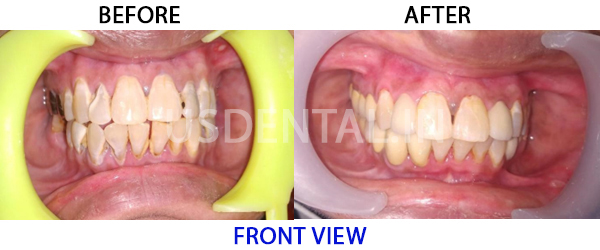

How to Deal with Pyorrhea? Patient has visited us with the chief complaint of multiple upper and lower loose teeth.…

How to Deal with Pyorrhea? Patient has visited us with the chief complaint of multiple upper and lower loose teeth.…